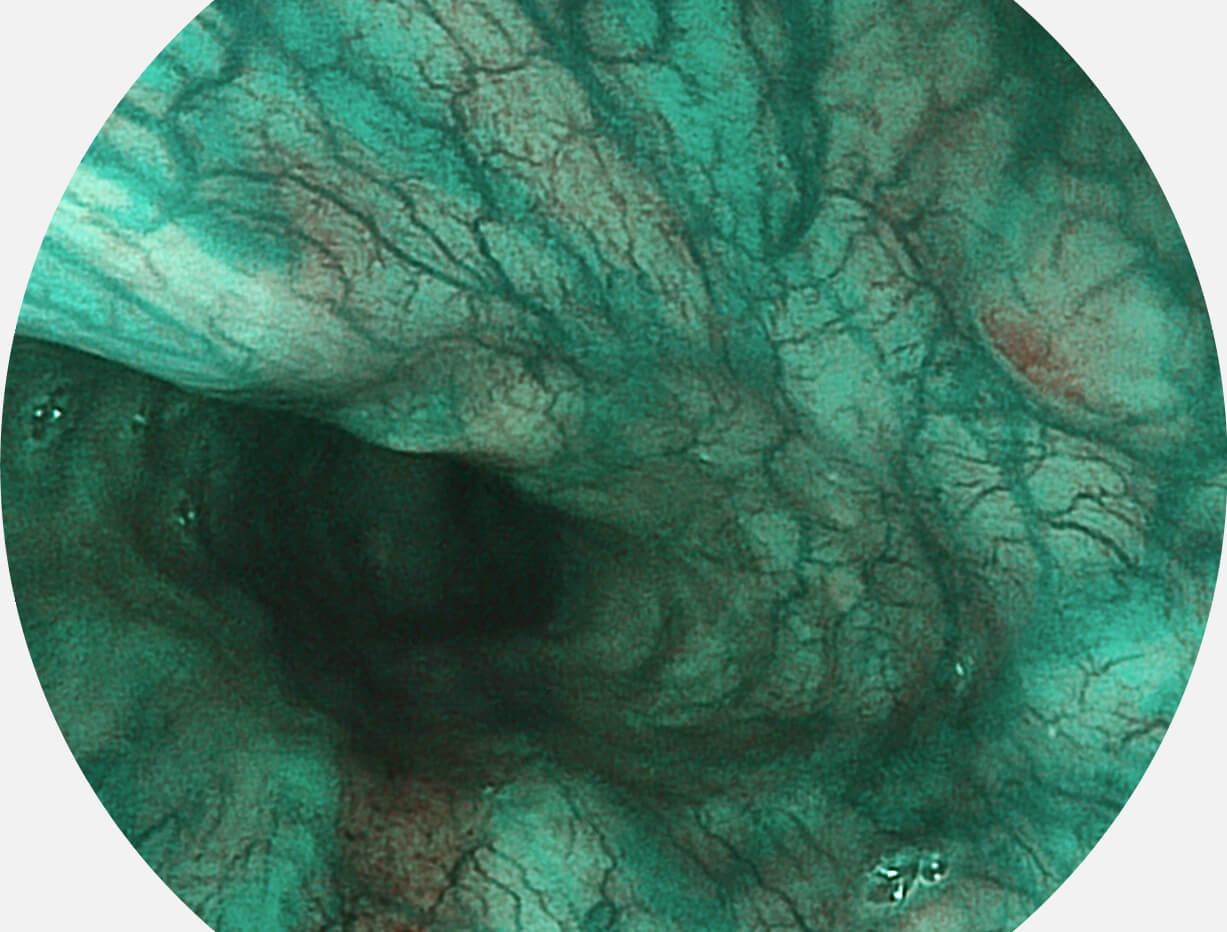

• 白光图像 VIST图像

强调浅层黏膜结构的同时,保证照明亮度和提升浅层微血管与中层血管颜色对比度,病变边界更清晰。